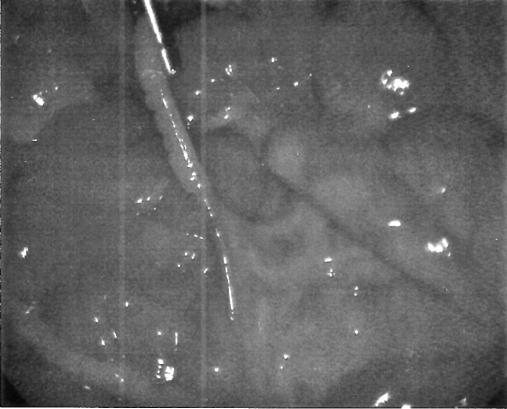

Small bowel obstructions are most frequently caused by hernias or adhesive bands. However, there have been several rare reported cases of mechanical small bowel obstructions caused by loops of bowel or vascular bands. We describe a case of a 30-year-old woman with a clinical presentation suggestive of appendicitis. Laparoscopic evaluation showed an aberrant vessel looping around the small bowel extending from the lateral anterior abdominal wall to the mesoappendix, resulting in a partial small bowel obstruction. We review the literature relating to bowel obstructions resulting from bowel knots and vascular bands. To our knowledge, this is the first reported case of a small bowel obstruction caused by an aberrant intraabdominal vessel.

小肠梗阻最常见的病因是疝气或粘连带。然而,有几例罕见的由肠袢或血管带导致的机械性小肠梗阻病例报告。我们描述了一例30岁女性患者,其临床表现提示阑尾炎。腹腔镜检查发现一条异常血管从小腹前外侧壁延伸至阑尾系膜,环绕小肠,导致部分小肠梗阻。我们回顾了与肠结和血管带所致肠梗阻相关的文献。据我们所知,这是首例由腹腔内异常血管导致小肠梗阻的病例报告。